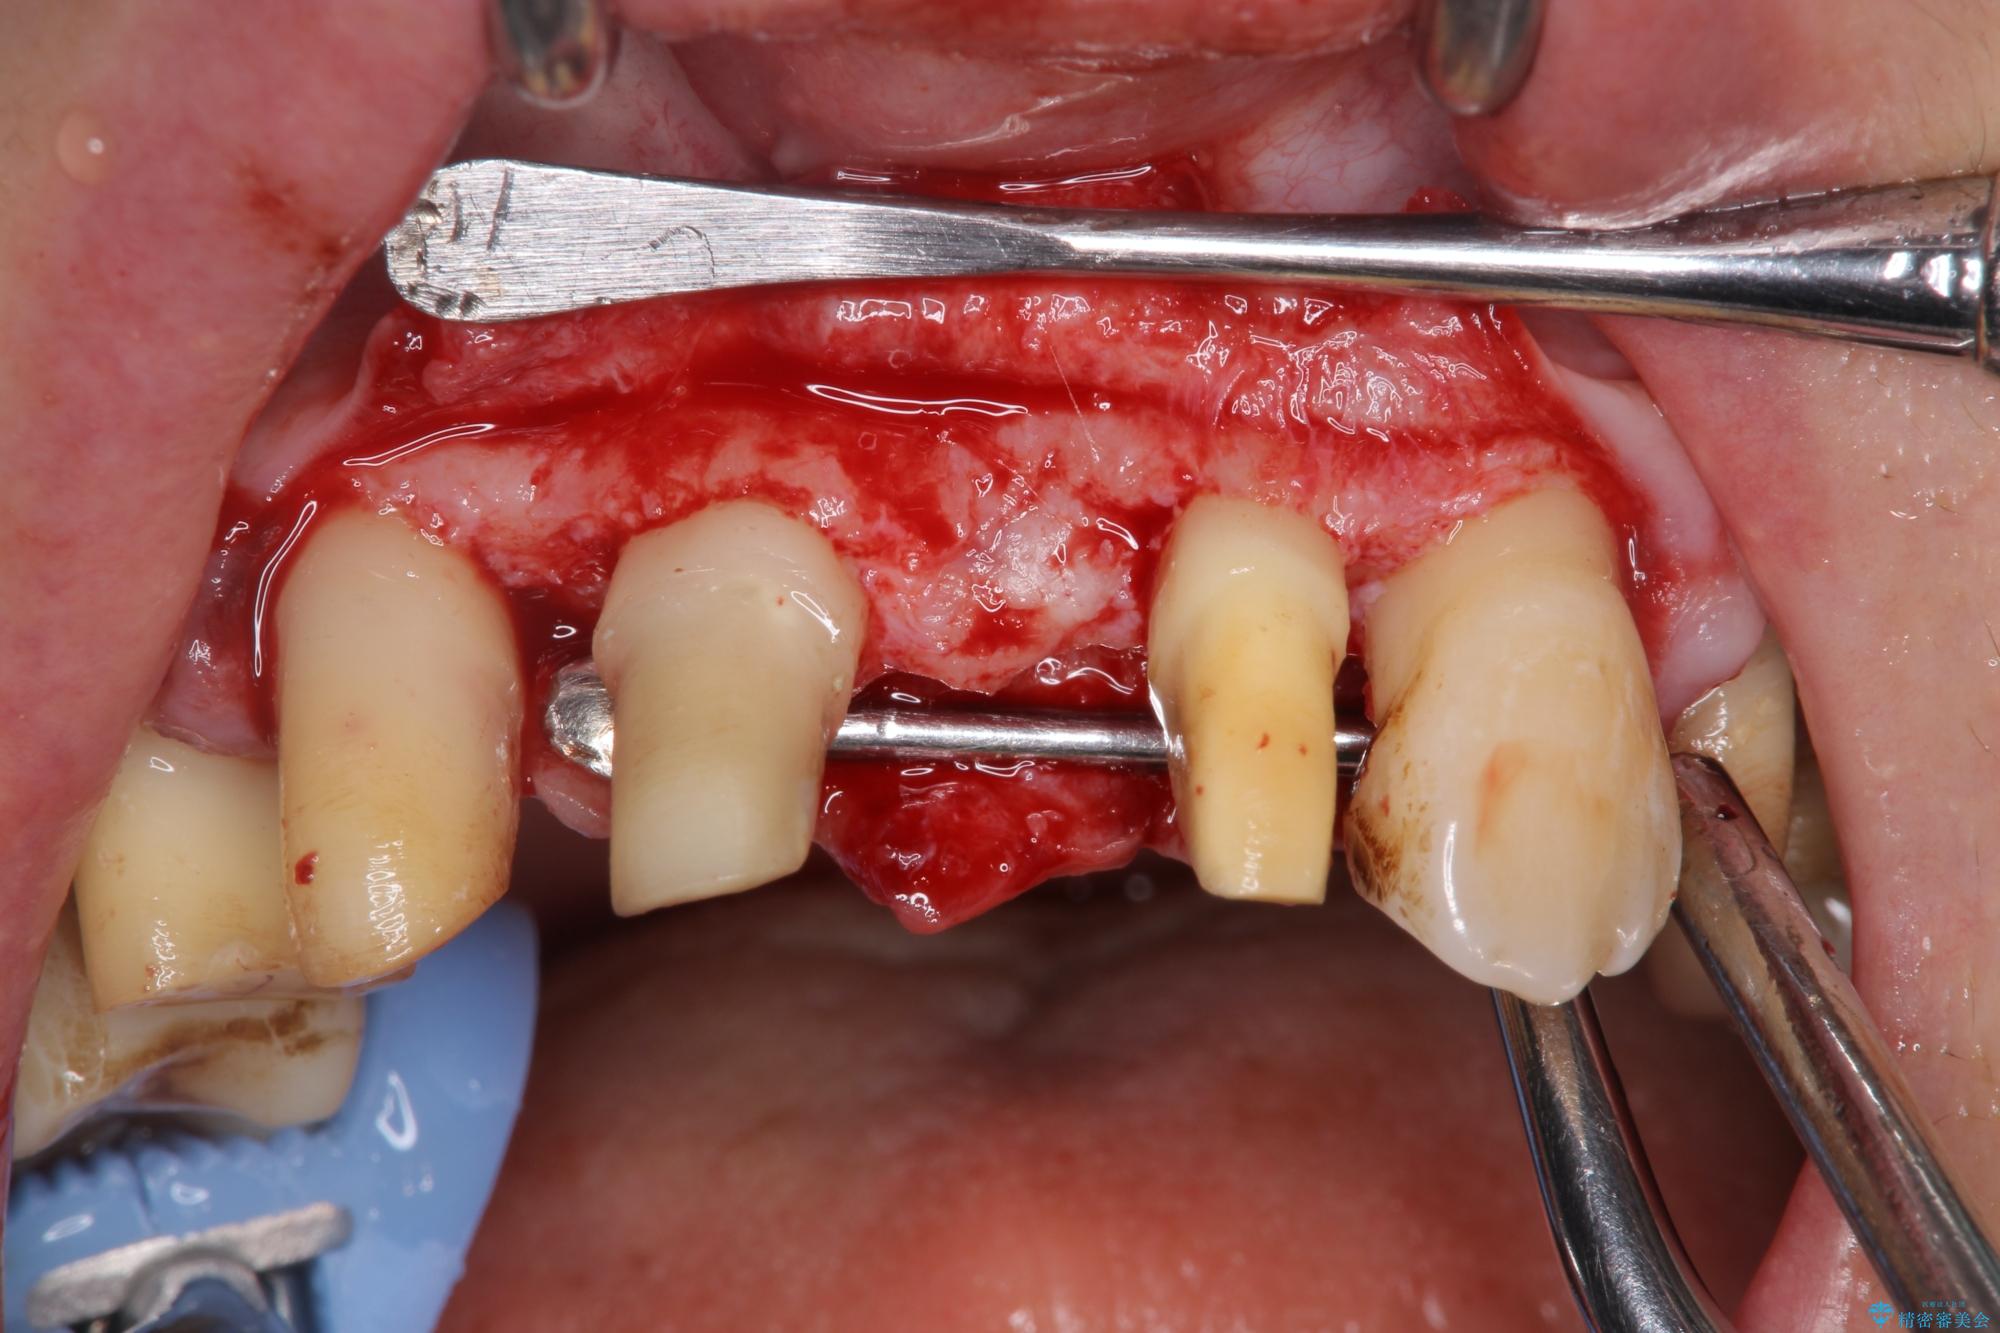

まず、保存の難しい歯を抜去したのち矯正治療を行い歯並びの改善、歯周ポケットを除去したことで安定した歯周環境、咬合関係を作り出すことができました。

治療中

歯の総合的なマネージメントを行う包括的歯科治療の実践[ 歯周病・矯正・セラミック補綴 ] 治療中画像 歯の総合的なマネージメントを行う包括的歯科治療の実践[ 歯周病・矯正・セラミック補綴 ] 治療中画像 歯の総合的なマネージメントを行う包括的歯科治療の実践[ 歯周病・矯正・セラミック補綴 ] 治療中画像 歯の総合的なマネージメントを行う包括的歯科治療の実践[ 歯周病・矯正・セラミック補綴 ] 治療中画像 歯の総合的なマネージメントを行う包括的歯科治療の実践[ 歯周病・矯正・セラミック補綴 ] 治療中画像 歯の総合的なマネージメントを行う包括的歯科治療の実践[ 歯周病・矯正・セラミック補綴 ] 治療中画像 歯の総合的なマネージメントを行う包括的歯科治療の実践[ 歯周病・矯正・セラミック補綴 ] 治療中画像 歯の総合的なマネージメントを行う包括的歯科治療の実践[ 歯周病・矯正・セラミック補綴 ] 治療中画像 歯の総合的なマネージメントを行う包括的歯科治療の実践[ 歯周病・矯正・セラミック補綴 ] 治療中画像 歯の総合的なマネージメントを行う包括的歯科治療の実践[ 歯周病・矯正・セラミック補綴 ] 治療中画像 歯の総合的なマネージメントを行う包括的歯科治療の実践[ 歯周病・矯正・セラミック補綴 ] 治療中画像